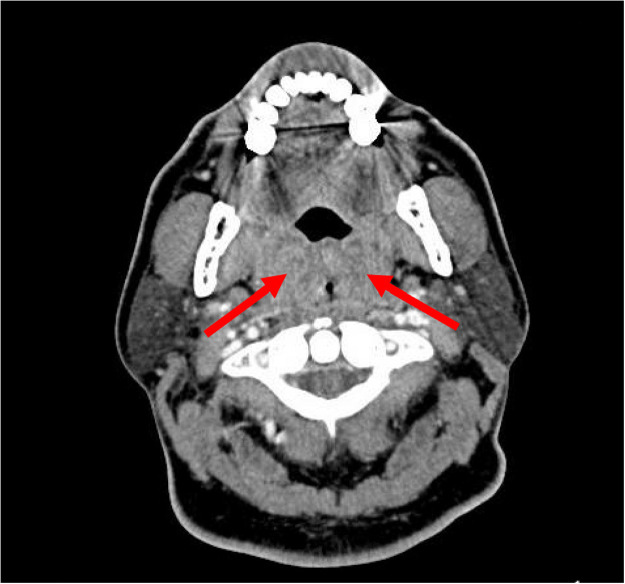

Four days after the second presentation, she returned to the ED with severe odynophagia, new dysphagia, and dysphonia. On physical examination, the patient had a temperature of 36.6°C, heart rate of 95 beats/min, blood pressure of 117/84 mm Hg, and oxygen saturation of 100% on room air. She had a muffled voice, bilateral tonsillar swelling with exudates, and tender cervical adenopathy. Her white blood cell count was 9.53 × 109 cells/L. Rapid mononucleosis testing returned negative. Computed tomography (CT) of the neck soft tissue with contrast revealed significantly enlarged bilateral tonsils with small abscesses and severe airway narrowing (Figure 1 ).

Figure 1.

Computed tomography of neck soft tissue with contrast. Enlargement of the left and right tonsils (arrows) and adjacent soft tissues with marked narrowing of the airway in this region. There may be small hypodensities in the tonsils potentially representing small abscesses.